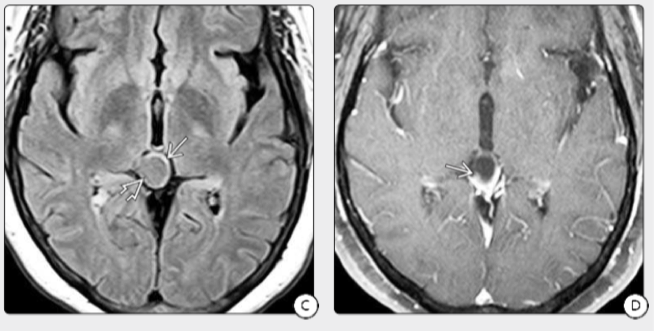

图3:A.一名58岁头痛且正常神经系统检查的妇女T2WI显示混合的囊性和实心松果体压迫了顶板。B.T1WI显示肿块囊性部分比相邻三脑室的CSF高。C.FLAIR MR显示囊肿中的液体相未被控制,无阻塞性脑积水。D.T1 C+FS MR肿瘤的实质部分显示出异质性强化。